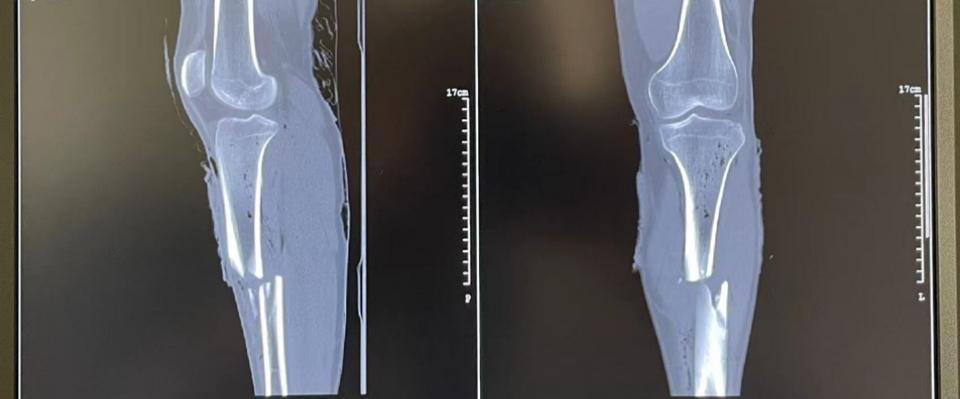

快递小哥逆向行驶,撞倒一名骑自行车的男子。 男子左侧小腿严重骨折,被紧急送往医院。 医生决定采用一种先进的手术方法——髓内钉固定术。 术后仅两天,患者就能下地活动了。这个案例展示了现代骨科技术的神奇力量。

以一位25岁患者的案例为例。他因车祸导致左侧胫骨中段骨折。医生采用髓内钉固定术, 手术仅用了50分钟。 术后第二天,患者就能在医生指导下下地活动。3个月后,他就能正常行走,几乎看不出曾经受过伤。这个案例充分展示了髓内钉固定术的优越性。